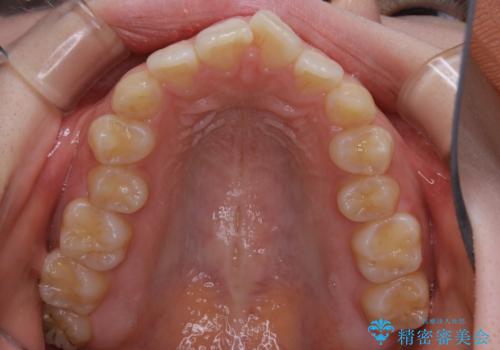

- 前歯の重なりが気になるとご相談にいらした方です。前歯のがたつきは奥歯の噛み合わせのズレが原因となっていたため、インビザラインFULLにて奥歯からしっかり治療していきました。

前歯のがたつきだけを治そうとした場合、噛み合わせは二の次なってしまう事が多く、せっかく綺麗になった歯並びも後戻りしやすくなります。

見た目だけでなく奥歯を移動させて噛み合わせの改善までが行えるのはインビザラインであるからこそです。奥歯の噛み合わせからしっかり機能させることで、長期間にわたって綺麗な歯並びを保ちやすくなります。